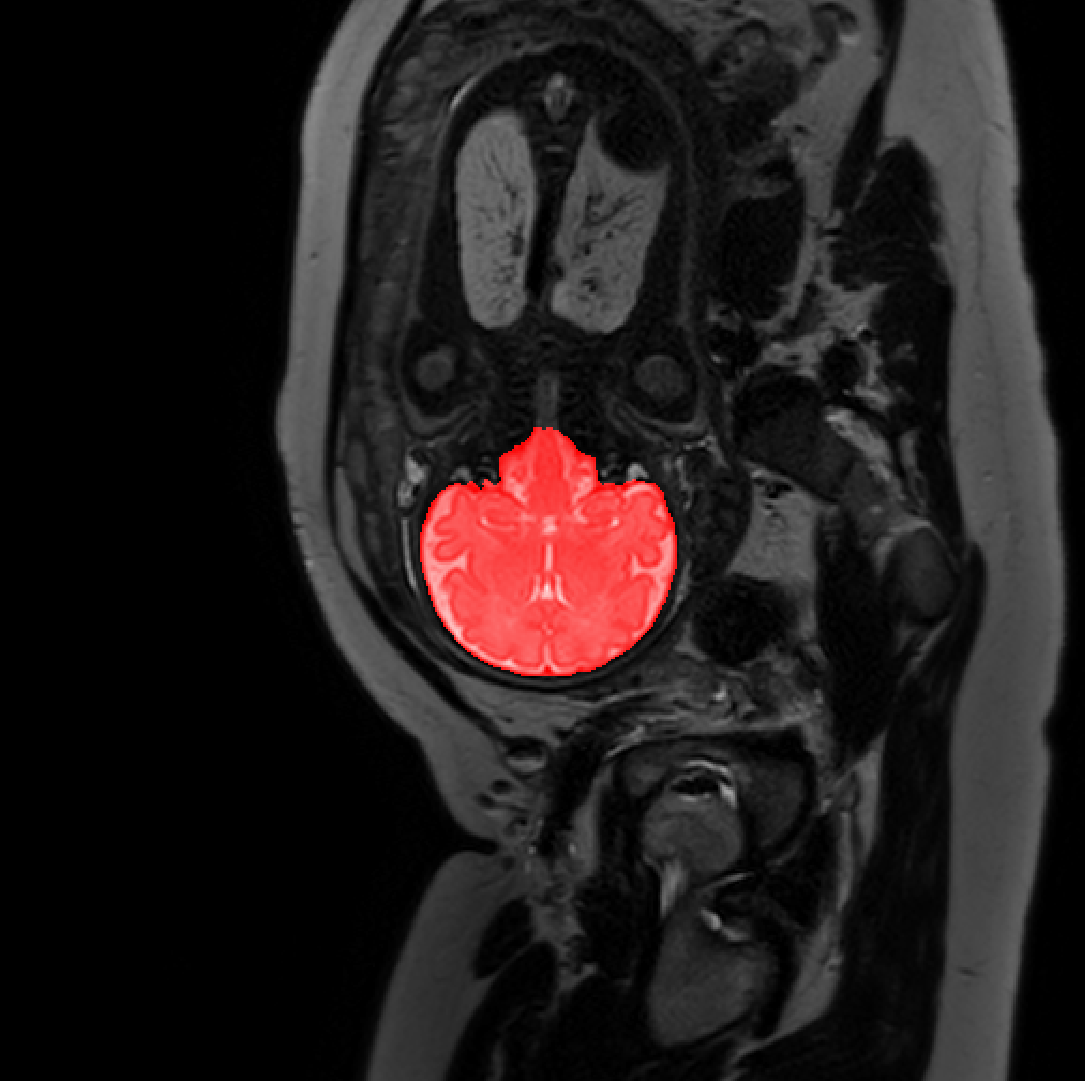

Table 1 lists average of quantitative evaluation results of these experiments and Figure 2 shows results obtained from each image. Figure 3 shows examples of the obtained segmentations.

Refer to caption

Figure 3: Example of ICV segmentations in images acquired in axial (left), coronal (middle) and sagittal (right) planes. Top row: A slice from T2-weigted image; Second row: Automatic segmentations obtained using 7 training images from the representative imaging planes; Third row: Automatic segmentations obtained using all 21 training images from all 3 image orientations; Bottom row: Manual segmentation.